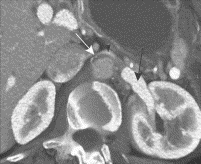

Our own great cardiologist, Kim Eagle, years back as editor of the NEJM section Images in Clinical Medicine, published a classic image of a 52 year-old woman with mild episodic gross hematuria from renal vein compression by the superior mesenteric artery. [Kimura & Araki. NEJM. 335:171, 1996] Improved CT technology offers a better image (below) in a more recent paper from the Mayo Clinic Proceedings. [Kurklinsky & Rooke. Mayo Clinic Proceedings 85:552, 2010]

[Computed tomographic venogram: nutcracker phenomenon.

Distended left renal vein (black arrow) compressed between

aorta and superior mesenteric artery.]